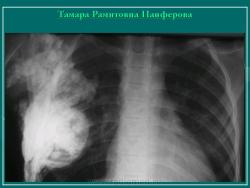

Думаю что это обызвествлённая гематома мягких тканей.

Анамнез не помешал бы.